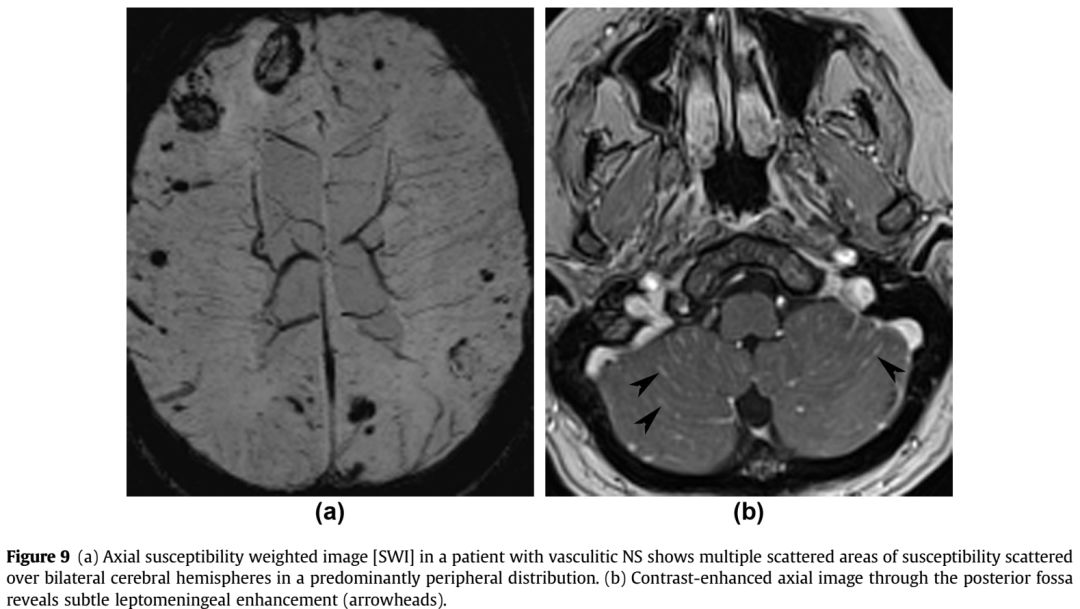

增强序列可见双侧额叶软脑膜明显强化并沿软脑膜侵入沟回,左侧颞顶交界区小片状强化;冠状位及FLAIR可见皮层皮下之白质亦有波及。该病例只有磁共振,且只有FLAIR和增强两个序列,但给人的信息量并不少:脑膜尤其是软脑膜受累突出,伴有皮层、实质损害,强化明显。感染、肿瘤、非感染性炎症都有可能,到底是什么呢?

诊断: 神经结节病

结节病是一种病因不明的多系统肉芽肿性炎症性疾病,年轻人多见。全世界的发病率各不相同,约为10-20/100,000人。它主要影响肺,皮肤和眼睛,神经系统受累约占5-20%。可以说神经结节病是罕见病中的少见表现,但其影像学具有一定的特点,也容易与其他疾病混淆,了解了这些特点在日后不期而遇时不会让它从眼皮下溜走。神经结节病影像学最突出的特点是软脑膜受累,但只知道软脑膜是不足以全面掌握神经结节的影像学表现,关于神经系统其他受累部位及鉴别诊断如下图:

➤表现为出血:

➤脑干胡椒粉改变: